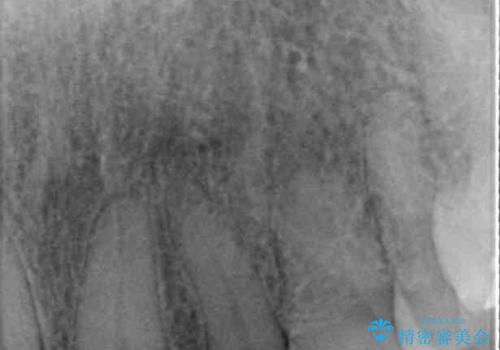

診査の結果、既に歯の神経は失活していたおり、叩いたり触ったりしたときの痛みも確認されました。

まずは根管治療を行い、その後にオールセラミッククラウンにて補綴することとしました。

補綴後6ヶ月経過しレントゲンを撮影したところ、歯根周辺に病変認められず、良好な経過をたどっていることが分かりました。